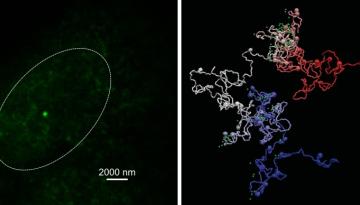

A continuació es mostren alguns projectes destacats que van rebre finançament el 2022 mitjançant convocatòries tant competitives com no competitives per part d’entitats públiques i privades. Aquests i altres projectes estratègics han pogut avançar gràcies a l’ús de tecnologies d'última generació, com ara l'aprenentatge automàtic, la intel·ligència artificial i la seqüenciació de cèl·lules úniques.